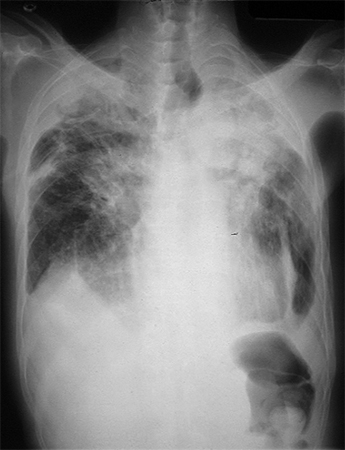

Os pacientes com silicose e com pneumoconiose dos trabalhadores de carvão podem apresentar opacidades arredondadas na radiografia torácica. Com a evolução para doença avançada, há uma aglomeração de pequenos nódulos, formando opacidades grandes que podem cobrir todo o lobo superior. Um indivíduo com silicose simples leve ou pneumoconiose dos trabalhadores de carvão geralmente apresenta opacidades q ou r, com profusão de categoria 1 ou 2. Na doença mais avançada, a profusão será de categoria 3. Na doença ainda mais grave (fibrose maciça progressiva), haverá grandes opacidades A, B ou C.

Alterações pleurais são observadas na radiografia com exposição ao amianto e sem nenhum desses 3 tipos de pneumoconiose.[Figure caption and citation for the preceding image starts]: Radiografia torácica mostrando alterações consistentes com a silicose simples ou a pneumoconiose dos trabalhadores do carvãoDo acervo pessoal do Kenneth D. Rosenman, Michigan State University [Citation ends].